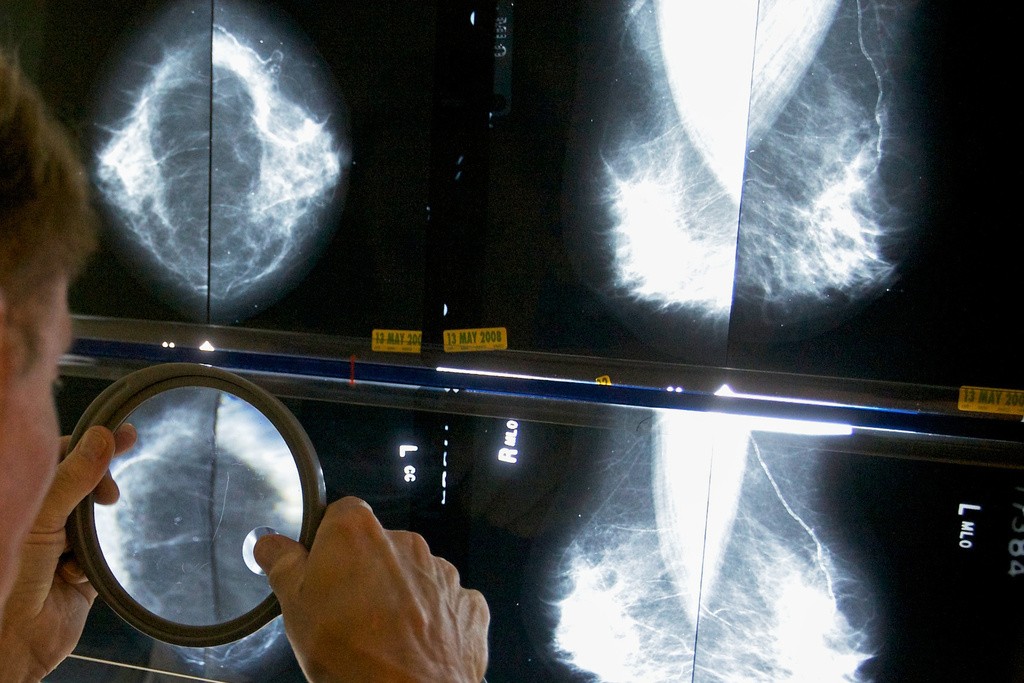

Radiologista usa lupa para examinar mamografias em busca de câncer de mama.

AP/Damian Dovarganes/Arquivo